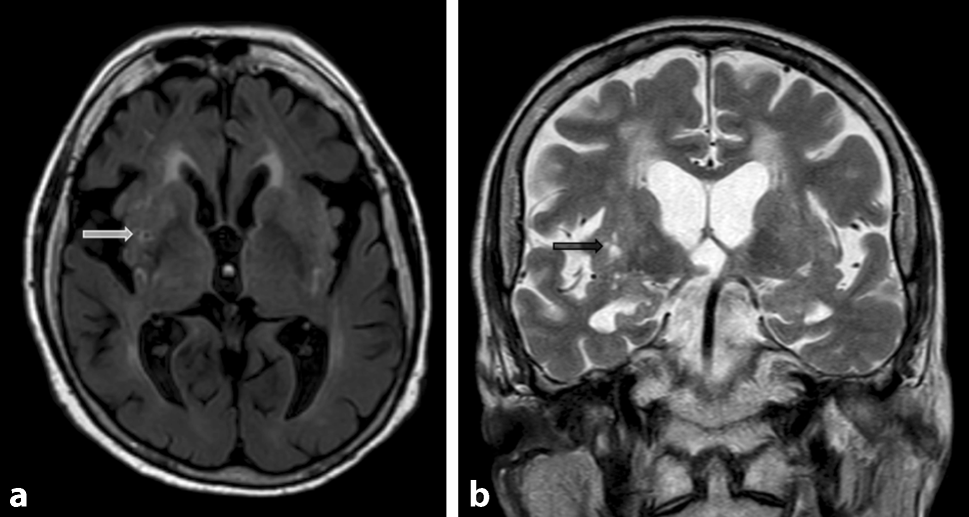

Lacunes and Virchow-Robin spaces

Lacunes are deep, small-vessel infarcts with a CSF-like signal on all MRI sequences (illustrated in Fig. 5). In contrast, Virchow-Robin spaces are enlarged perivascular spaces usually due to volume loss of the surrounding tissue with a predilection for the basal ganglia (illustrated in Fig. 6).

Fig. 5

Lacunes. Illustration of lacunes in the putamen (arrow) on axial Flair images (a) and coronal T2-weighted images (b)

Bild vergrößern